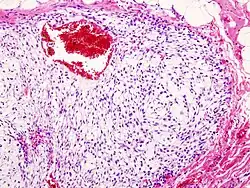

| Histopathologic image of chondrosarcoma of the chest wall. Surgical resection of recurrent mass. H & E stain. | |